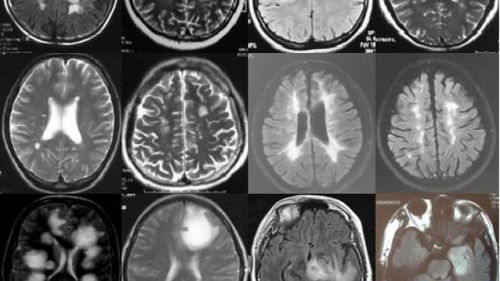

首先,我们要明白放疗是一种利用高能射线破坏肿瘤细胞DNA,从而达到治疗目的的方法。在脑瘤治疗中,放疗常用于手术前缩小肿瘤体积,或手术后消灭残余的肿瘤细胞。然而,放疗的效果并非一蹴而就,它需要时间积累才能达到预期的治疗效果。

脑瘤放疗需要一个月的时间,主要是因为放疗的效果与肿瘤细胞的生长周期和放疗的剂量累积效应有关。肿瘤细胞的生长周期较长,且不同肿瘤细胞的生长速度也不尽相同。因此,放疗需要持续一段时间,以确保对肿瘤细胞造成足够的杀伤。同时,放疗的剂量也需要逐步累积,以最大程度地减少正常细胞的损伤,同时保证对肿瘤细胞的杀灭效果。

那么,脑瘤放疗需要一个月是否意味着患者的病情无法挽回呢?答案是否定的。虽然脑瘤的治疗难度较大,但放疗作为一种有效的治疗手段,仍然可以在很多情况下为患者带来希望。放疗可以通过缩小肿瘤体积,降低颅内压,缓解患者的症状,提高生存质量。同时,放疗还可以为手术创造条件,提高手术切除的成功率。

当然,放疗并非万能。对于恶性程度较高的脑瘤,单纯的放疗可能无法完全控制病情。此时,患者需要在医生的指导下进行综合治疗,包括手术、化疗、中医治疗等多种手段的结合。此外,患者的个体差异、肿瘤类型、恶性程度等因素也会影响放疗的效果。因此,患者在接受放疗治疗时,需要保持积极的心态,与医生密切沟通,制定个性化的治疗方案。